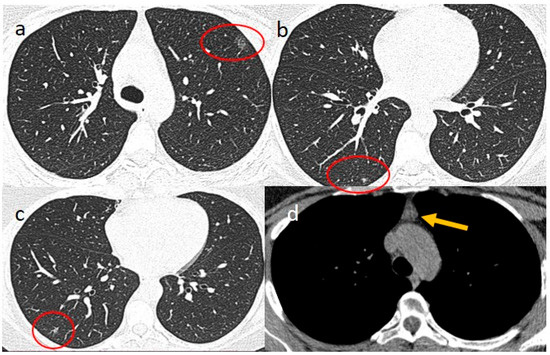

2. Case Presentations